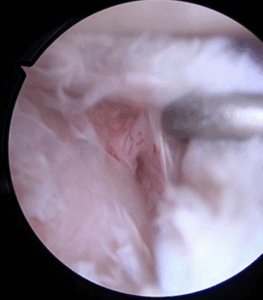

It was demonstrated that, despite the different concave shape of the glenoid, its OCD follows the same progression over the time of the convex weight-bearing articular surfaces and needs, likewise, the same gradespecific management. Patients with IRCS OCD stage I and some with OCD stage II present with a stable shoulder and can undergo conservative treatment. Unstable or advanced glenoid OCD stages, characterized by disruption of the articular cartilage and the presence of separated fragments as loose bodies, require surgical treatment. Moreover, this is indicated when the conservative approaches fail, especially because of long-standing pain and joint range of motion worsening. Proposed surgical treatments include arthroscopic drilling, microfractures, debridement of the unstable osteochondral fragments, and fixation with suture anchor or autogenous osteochondral plugs, platelet-rich plasma, and gellike sodium hyaluronate. (2,4) There is not yet consensus regarding the ideal technique. In this Technical Note, we describe an arthroscopic procedure with a single-layer hyaluronate-based scaffold for the treatment of OCD of the glenoid.